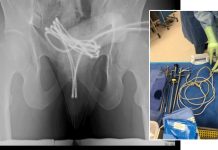

Homem é internado após enfiar cabo USB no pênis e objeto ficar preso

Um caso inusitado e preocupante foi relatado na revista médica Cureus, envolvendo um estudante universitário de 21 anos, nos Estados Unidos, que precisou ser...